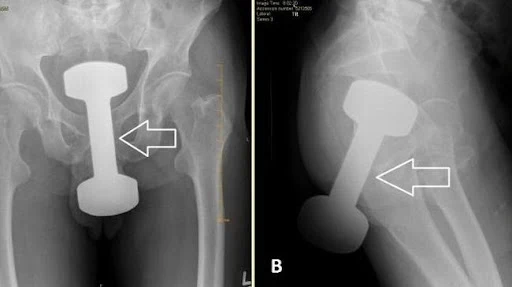

kasus medis langka yang bikin heboh. (foto: cureus journal)

AS, Sinata.id – Sebuah dumbel gym seberat 2,2 kilogram berhasil dikeluarkan dari dalam rektum seorang pria berusia 50 tahun di Pennsylvania, Amerika Serikat, setelah tersangkut selama beberapa jam. Kasus tidak biasa ini dipublikasikan dalam jurnal medis Cureus.

Tim medis kemudian melakukan serangkaian pemeriksaan. Pemeriksaan rektal menemukan benda logam keras, sementara radiografi menunjukkan bayangan benda asing berbentuk dumbel di panggul pasien. Tim bedah segera dikonsultasikan.